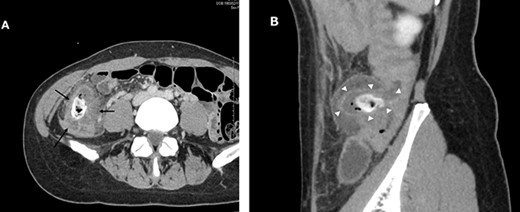

Laparoscopic findings showed that the inflammatory changes were not significant. The surgeon had expertise skills on multiport laparoscopic surgery (MLS) with some SILS experience. Initially, a 40-mm incision was made at the umbilicus. We then performed ileocolic mobilization and lymphadenectomy with ileocolic arterial and venous resection by SILS, similar to MLS (Fig. 3A). Functional end-to-end anastomosis was performed out of the body after removal through an umbilical incision (Fig. 3B and C). The operation time was 2 h and 47 min, and the amount of bleeding was minimal. Macroscopic findings of the surgical specimen showed a diverticulum with an ulcer in the cecal colon, but no fecalith (Fig. 4). Pathological findings showed deep ulceration and abscess formation with no malignant findings. The patient’s course was good, and she was discharged 8 days after the operation.

Intraoperative images. Image (A) demonstrating the anastomotic site (black arrows) and ileocolic artery and veinous dissection (white arrowheads). Image (B) showing the ileocecal region raised outside the body and a diverticulum (white arrowheads). Image (C) shows after closure.